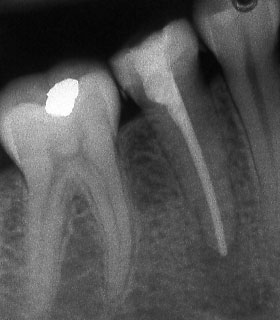

При наличие на огнище на възпаление около корените на зъба добре проведеното лечение води до изчезване на изменението. На снимката долу едва една седмица след пролекуване на каналите се наблюдава известна редукция на патологичния процес. За период от 6 месеца до 2 години е възможно да се наблюдава пълен оздравителен процес.

Понякога е налице патологичен процес около апекса на зъба, който налага да се проведе допълнителна хирургична намеса с цел отстраняване на лезията.